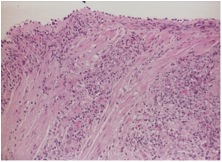

Excisional biopsy of submandibular gland with a diagnostic testing was performed. It showed lymphoid infiltrate with marked atrophy and perilobular and septal sclerotic fibrosis. The lymphoid infiltrate mainly consisted of small lymphocytes and large number of plasma cells. Immunohistochemical studies found most of the plasma cells positive for IgG and IgG4. So, the pathology suggested chronic sclerosing sialadenitis, consistent with IgG4-related disease. The ampulla specimen obtained in previous ERCP was also positive in IgG4 staining. The serum IgG4 level was checked and elevated to 102.9 g/L (normal range <2).

We reviewed the case and requested IgG4 staining for the transbronchial biopsy that obtained 3 months ago. The resulted showed many of the plasma cells positive cytoplasmic staining for both IgG and IgG4 (Fig 4A, 4B, 4C, 4D). It confirmed the pulmonary involvement of IgG4-related disease.